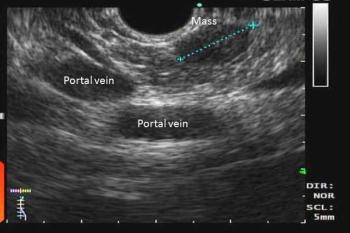

Intermittent blurred vision and palpitations in a young woman often improve after juice. She does not have DM. One day, she arrives at the ED after a seizure. Head CT is negative. What’s next?

Diet and medication can be used to manage symptoms of insulinoma. Once the lesion is well localized, resection is curative.